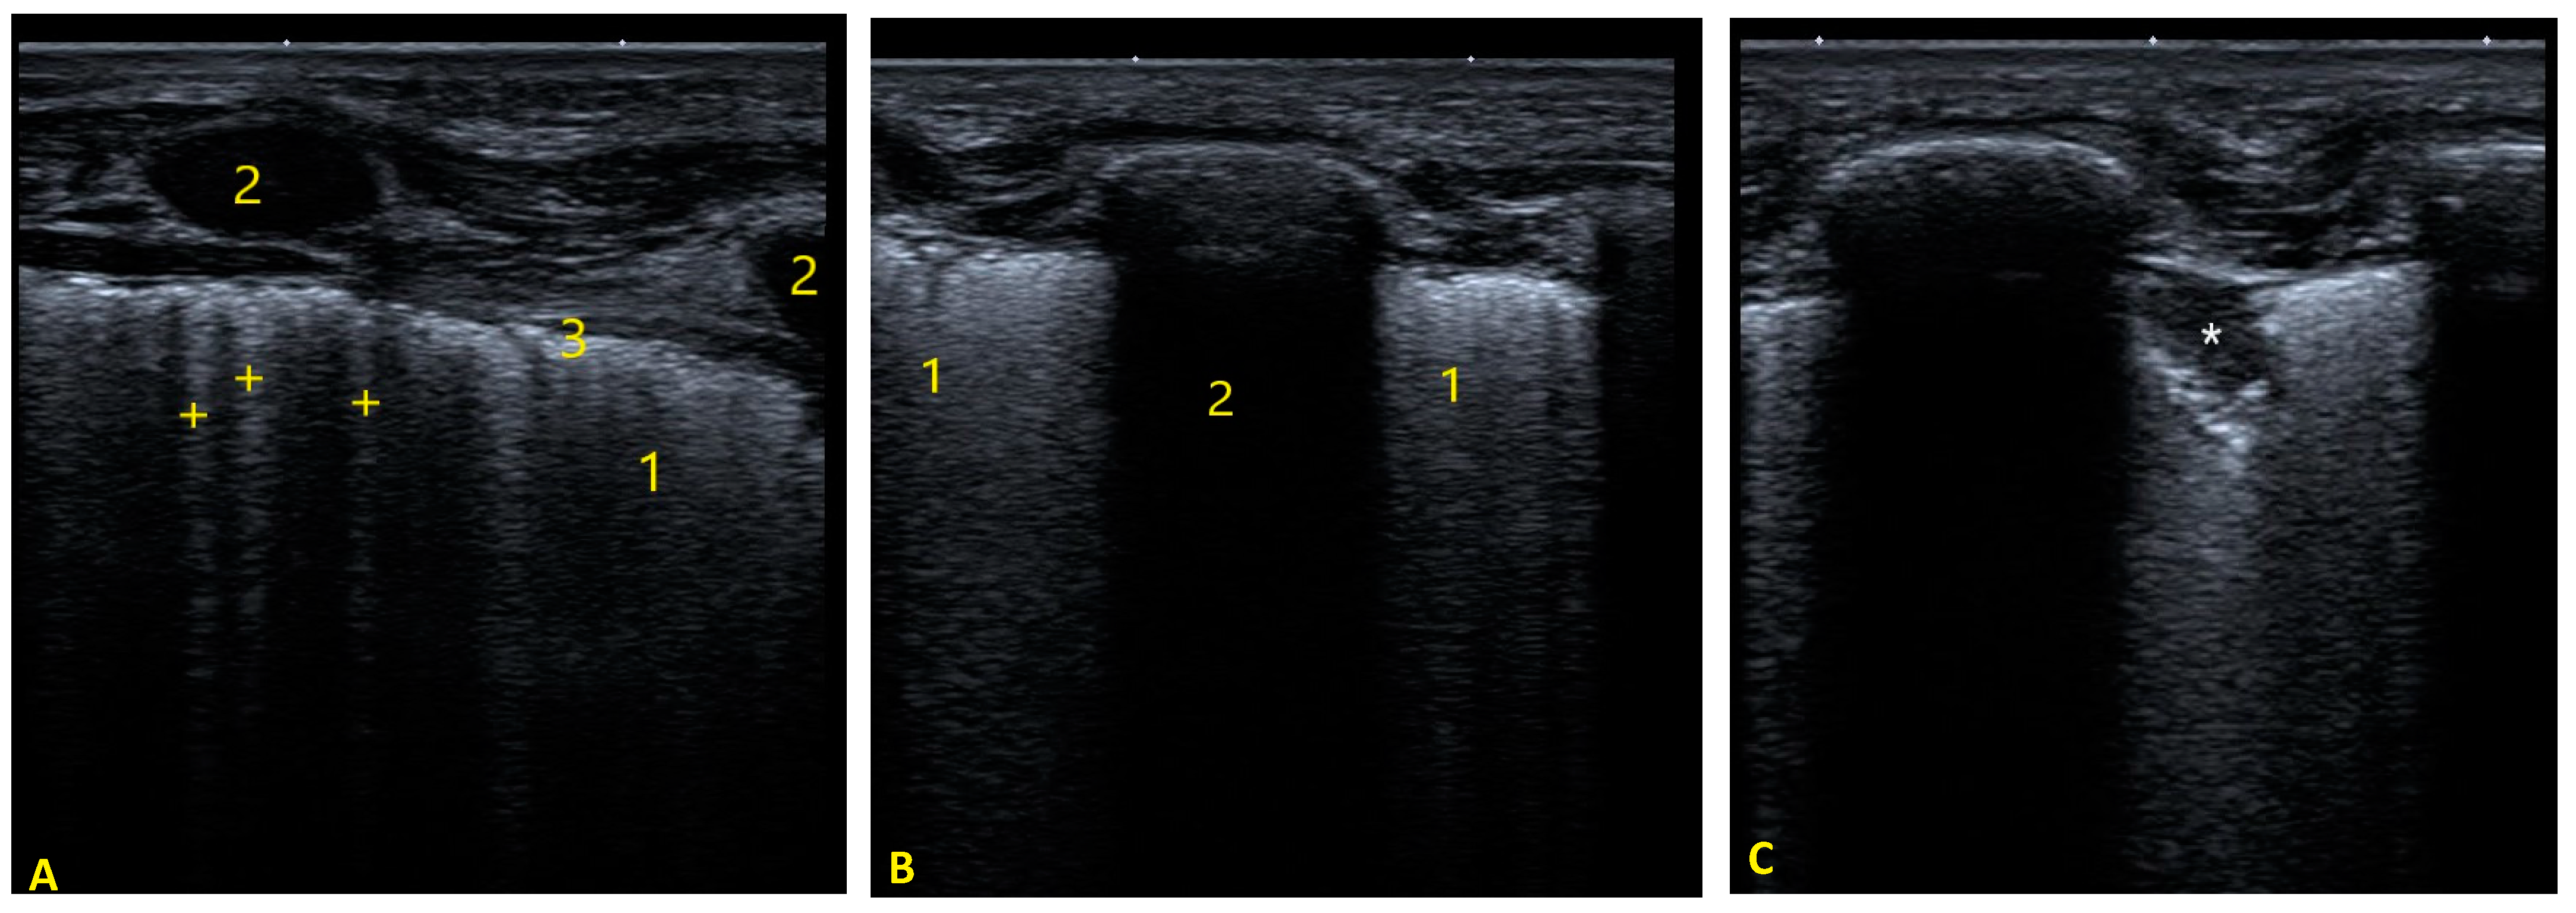

2.2.1. Pulmonary Status Assessment

4.1. Pulmonary Status in Acute Bronchiolitis